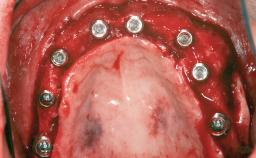

Le Fort I Interpositional Graft and Mandibular Sandwich Osteotomy for Maxillofacial Rehabilitation after Severe Periodontitis

A 47-year-old woman who had suffered from aggressive periodontitis requiring a number of periodontal interventions over more than 10 years was referred by her general dental practitioner and periodontologist for bone augmentation and implant therapy. Her failing dentition had already been scheduled for extraction. The patient expressed a desire for implant-supported fixed restorations and esthetic improvement of her lower face. She had agreed to consult with a maxillofacial surgeon after the referring dentist had suggested bone augmentation. An initial examination by the maxillofacial surgeon revealed mobility of all residual teeth in a patient who was very unhappy with the function of her removable partial dentures. Due to periodontally migrated flaring teeth and loss of occlusal support, the vertical dimension of occlusion was dramatically reduced. The patient was displeased with her lower face because of deepened nasolabial, commissural, and supramental folds.